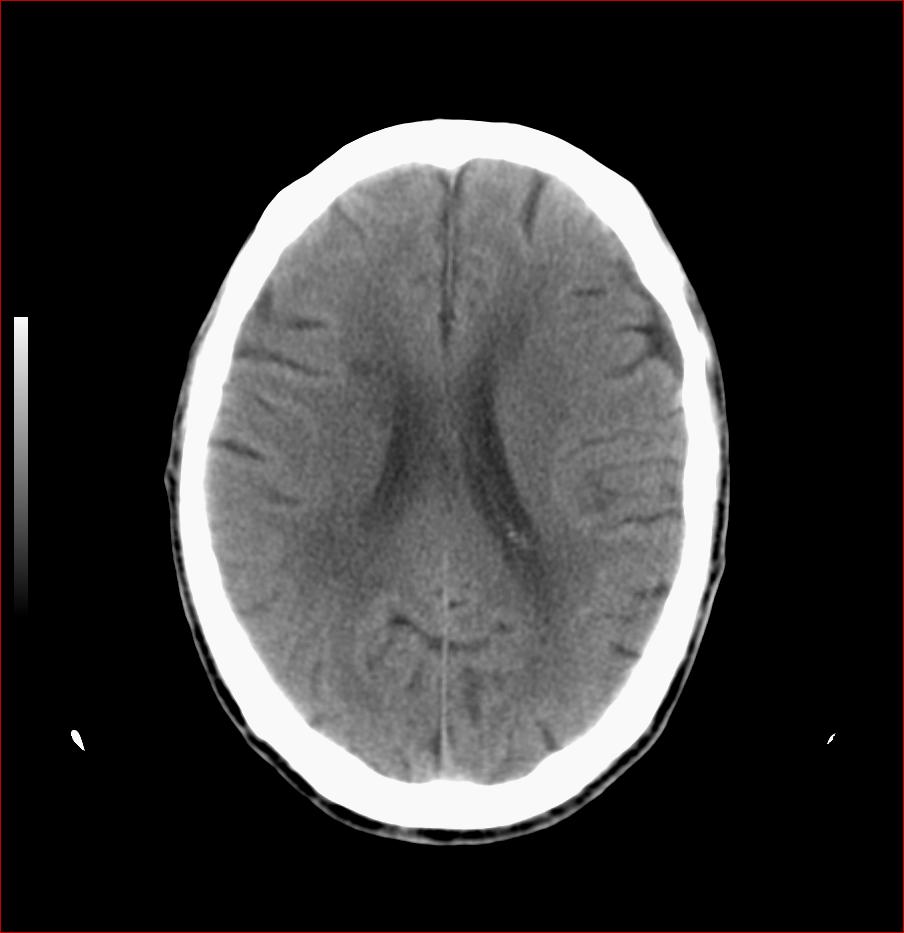

男,84岁,左下肢无力伴口角歪斜1天,血压160/80。请问一下双侧基底节区是脑梗塞吗?

多发脑梗塞,白质疏松,脑萎缩

双侧基底节多发腔梗,皮层下动脉硬化性脑病

老年性三联症_多发腔隙性梗死 脑萎缩 脱髓鞘变性.

双侧基底节多发腔隙性脑梗塞;脑白质蔬松;脑萎缩。

1.两侧基底节区及右顶深部脑梗塞。2.右侧外囊区脑软化灶。3.脑萎缩。4.脑白质脱髓鞘改变。

1.双基底节区及双顶深部脑梗塞;2.右外囊区软化灶;3.皮层下动脉硬化性脑病.